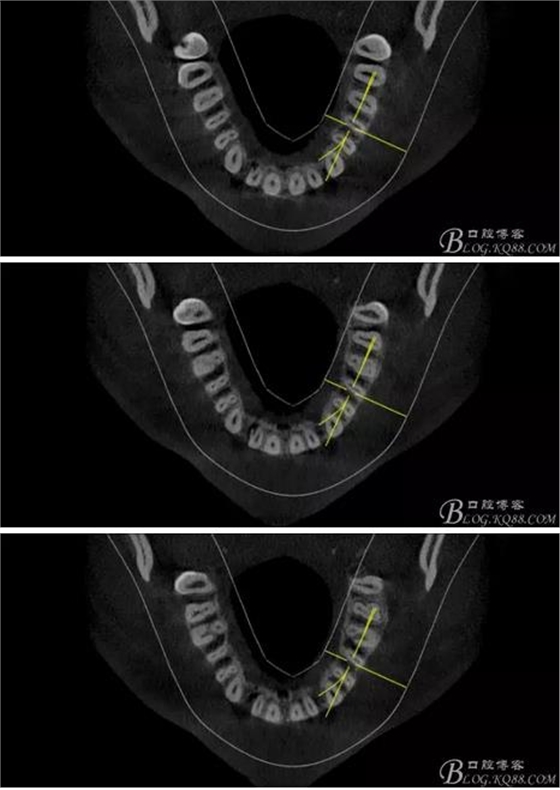

(1)檢查:12唇側(cè)牙齦可見竇道,牙體顏色較鄰牙暗,無光澤,形態(tài)完整無缺損,唇側(cè)及近遠(yuǎn)中向未提及牙周袋。腭側(cè)齦緣輕度紅腫,舌側(cè)窩可探及裂溝,可見浸墨狀痕跡,沿裂溝舌側(cè)探診牙周袋深大于11mm,除患牙外全口牙周狀況良好,為探及牙周袋,牙齦色粉紅。邊緣菲薄,質(zhì)地堅(jiān)韌。12冷熱診無反應(yīng),叩診(+-),無明顯松動(dòng),無咬合創(chuàng)傷。12根尖x線片示,根管中三分之一中可見一斜向線樣透射影像根尖區(qū)及遠(yuǎn)中根三分之一可見低密度透射暗影,錐形束CT示12根尖區(qū)唇腭向骨吸收已穿通,根面溝達(dá)根中三分之一卷曲分出另一牙根,再未見其他明顯的根管系統(tǒng)。